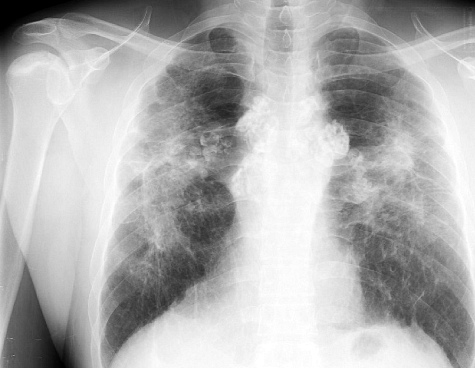

По статистике, у 40% больных диагноз выставляется по результатам изучения клинических симптомов и рентгенологического снимка легких. В остальных случаях окончательная диагностика требует проведения биопсии. При этом у пациента с подозрением на саркоидоз легких хирургическим путем изымается небольшая часть видоизмененной ткани. Гистологический и цитологический анализ биоптата определяет окончательный диагноз.

Пациенту необходимо помнить, что диагностическое исследование следует проходить у квалифицированного специалиста. Это связано с тем, что дифференциация гранулемного поражения проводится с диссеминированным туберкулезом и раком бронхоальвеолярной локализации.

- Компьютерную и магнитно-резонансную томографию.

Как диагностируется саркоидоз легких и как это влияет на риск рака?

Диагностика саркоидоза легких обычно включает рентгенографию грудной клетки, компьютерную томографию и биопсию легочной ткани. Если у пациента уже есть диагноз саркоидоза, важно регулярно проходить обследования, так как это может помочь в раннем выявлении возможных изменений, связанных с риском рака. Однако наличие саркоидоза не означает, что рак обязательно разовьется.